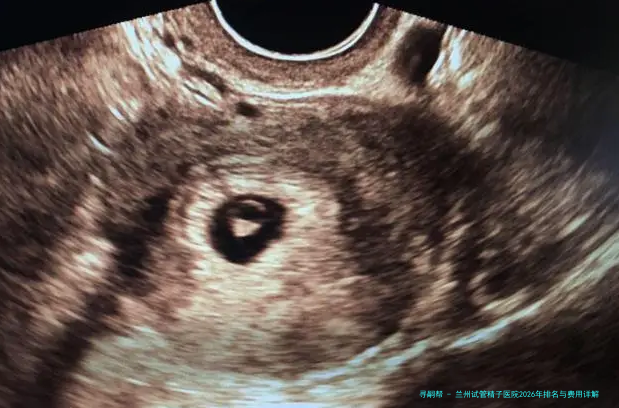

对于众多渴望享有自我孩子的家庭来说,辅助生育技术,特别是试管婴儿技术,就是他们实现梦想的重要路径。在兰州,选择一家技术靠得住、服务优质且收费透明的医院极为重要。今天,我们就来详细探讨一下兰州地区在试管婴儿,特别是涉及精子相关技术服务方面的医院情况,并为大家剖析相关的费用组成。